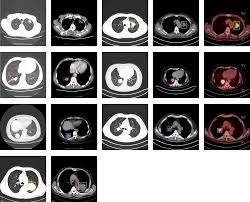

A Large Scale Ct And Pet Ct Dataset For Lung Cancer Diagnosis Lung Pet Ct Dx The Cancer Imaging Archive Tcia Public Access Cancer Imaging Archive Wiki from wiki.cancerimagingarchive.net Bone scans look for cancers that may have spread (metastasized) from other places to the bones. Pet/ct imaging helps to determine where a primary tumor is located. They are also used to assess if treatment is being effective in eliminating cancer. It provides 3d color images of the cells of your body. Cancer, including breast cancer, lung cancer and thyroid cancer. Then because of its high degree of specificity, pet/ct helps with radiation treatment planning. It may help identify a variety of conditions, including many cancers, heart disease and brain disorders. Brain disorders, such as brain tumors, epilepsy, dementia and alzheimer's disease.

Help diagnose and manage central nervous system disorders such as depression, epilepsy, alzheimer's and parkinson's disease. Because of this high level of chemical activity, cancer cells show up as bright spots on pet scans. Coronary artery disease, heart attack or other heart problems. With that being said, not all cancers can be detected by pet. A pet scan is similar to a ct scan; Pet is primarily used to diagnose cancer, cardiovascular disease, and neurologic disorders. Before the scan, you receive an injection of a tracer called radioactive glucose. Pet scans can help detect cancer and how far it has spread. The pet/ct scanner produces an image of the anatomy fused with the functional images of the use of sugar by cells. Doctors often order pet scans to stage a cancer or to assess whether treatment is working. Do all cancers show up on pet scan? The scans can also evaluate the occurrence of colorectal, lymphoma, melanoma, and pancreatic tumors. Brain disorders, such as brain tumors, epilepsy, dementia and alzheimer's disease.

Best Scans To Detect Cancer Envision Radiology from www.envrad.com Coronary artery disease, heart attack or other heart problems. Once you're ready to start the scan, you'll be asked to lie on your back on a platform. The use of pet scans may help doctors more accurately detect the presence and location of cancer cells. To determine whether the cancer has spread to the lymph nodes However, as with most studies, there are a few exceptions. However, pet scans can detect live cancer tissue. The parts of the body that need the most energy and the energy they use is sugar (also called glucose). Types of cancer detected and treated in the world of oncology, pet/ct is often used to detect breast cancer, lung cancer, stomach and pancreatic cancers, gi tumors, lymphoma, melanoma and much more.

Cancer cells have a higher metabolic rate than noncancerous cells. The pet/ct scanner produces an image of the anatomy fused with the functional images of the use of sugar by cells. Before the scan, you receive an injection of a tracer called radioactive glucose. A pet scan is similar to a ct scan; A pet scan uses a special substance, this substance is called tracker and is almost exactly like sugar, but has a small radioactive part. However, pet scans can detect live cancer tissue. Cell growth can be detected with a pet scan, but not all cancer types can be seen. Because of this high level of chemical activity, cancer cells show up as bright spots on pet scans. Information on other radiotracers and their use can be found in the molecular imaging and contrast agent database. There are many different radiotracers used in pet scans that take advantage of other cellular processes. Because cancer cells often take up more glucose than healthy cells, the pictures can be used to find cancer in the body. Pet scans usually use a form of radioactive sugar. Pet scans can be useful for evaluating people after breast cancer has already been diagnosed, in a number of different ways: